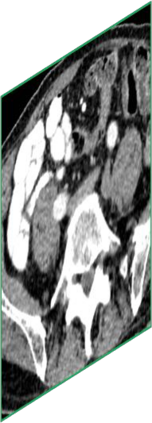

Due to the constraints of the imaging device and high cost in operation time, computer tomography (CT) scans are usually acquired with low intra-slice resolution. Improving the intra-slice resolution is beneficial to the disease diagnosis for both human experts and computer-aided systems. To this end, this paper builds a novel medical slice synthesis to increase the between-slice resolution. Considering that the ground-truth intermediate medical slices are always absent in clinical practice, we introduce the incremental cross-view mutual distillation strategy to accomplish this task in the self-supervised learning manner. Specifically, we model this problem from three different views: slice-wise interpolation from axial view and pixel-wise interpolation from coronal and sagittal views. Under this circumstance, the models learned from different views can distill valuable knowledge to guide the learning processes of each other. We can repeat this process to make the models synthesize intermediate slice data with increasing inter-slice resolution. To demonstrate the effectiveness of the proposed approach, we conduct comprehensive experiments on a large-scale CT dataset. Quantitative and qualitative comparison results show that our method outperforms state-of-the-art algorithms by clear margins.